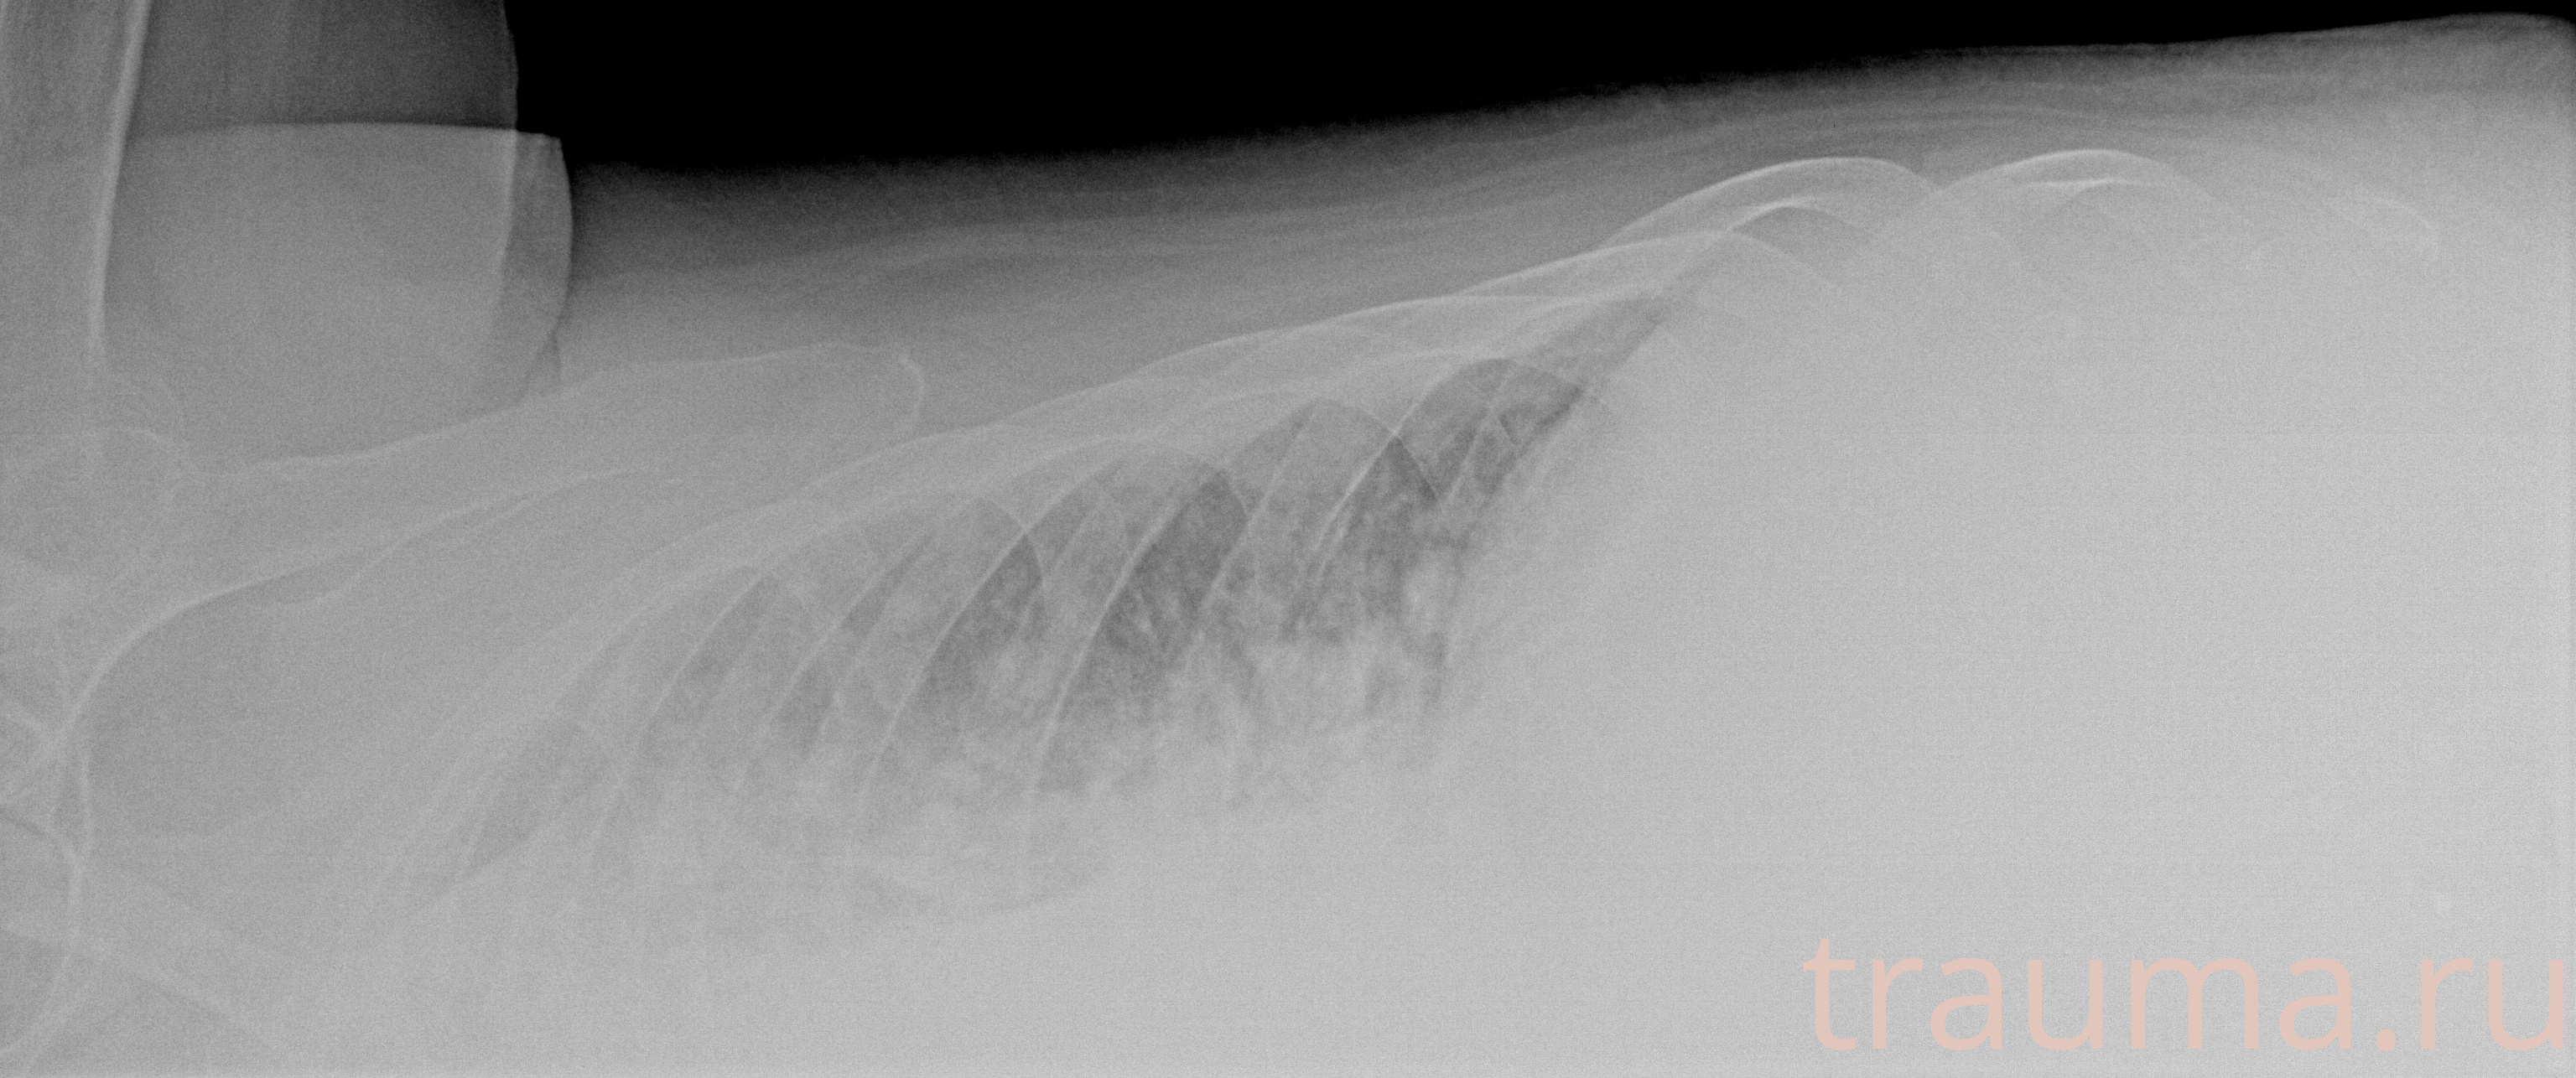

Рентгенограммы

Рентген на дому: по вашему адресу приезжает врач-рентгенолог, травматолог-ортопед с мобильным рентгеновским аппаратом, проводит диагностику травмы или заболевания, делает необходимые рентгенограммы, дает рекомендации по дальнейшему лечению. Получить качественные снимки в домашних условиях возможно благодаря уникальной методике, разработанной МосРентген Центром для института  Склифосовского